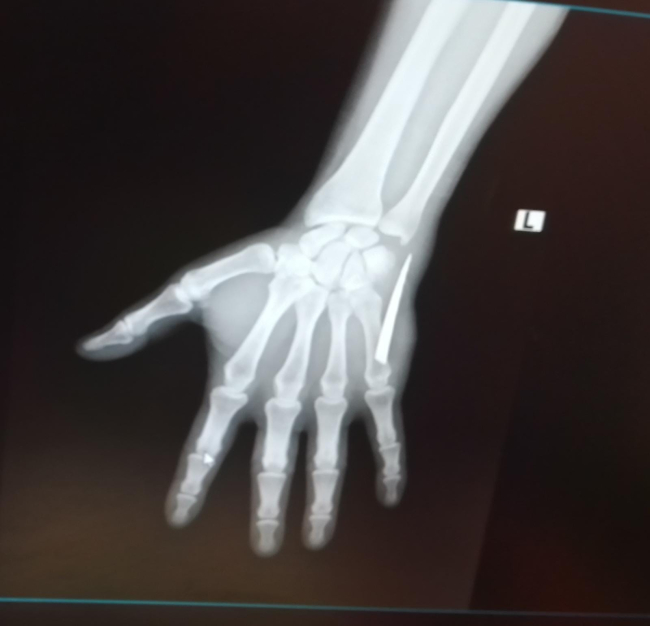

İddialara göre röntgen çekilmeden eline yapılan zımba dikişi sonrası 5 santimetrelik bıçak parçasıyla yaşamaya başlayan Köşeli enfeksiyondan kaynaklandığı belirtilerek, başka bir sıkıntı olmadığı gerekçesi ile tekrar evine gönderildi. Genç adam yaşadığı acı dolu günleri anlattı.

28 Kasım Pazartesi günü daha şiddetli bir ağrıyla uyandım. Elime baktığımda bir parça olduğunu hissettim. Küçük bir parça sandım eşimle almaya çalıştık ama baya büyük olduğunu fark ettik. Bunun üzerine Çaycuma Devlet Hastanesi’ne geldik. Hemen röntgen çekildi ve elimdeki parçanın baya büyük olduğu söylenildi. Sonrasında ameliyat ile bıçağın parçasını aldılar."

Kan kaybı yüzünden kan oranlarımda da düşüklük çıktı. Kanama olmasına rağmen iyice temizlemeye çalıştım. O esnada elimin içinde bir şey olduğunu fark ettim. Elimle dışarıdan doğru ittirmeye başladım. Yüzeye doğru parça geldi. Korkutan gerçek, Çaycuma Devlet Hastanesi’ne gelince meydana çıktı. Çıkan parçada gördünüz gibi büyük ve tırtıklı bir bıçak. Tırtıklı bıçak normal bıçak yüzüne göre daha zararlı. Kolumda da baya hasar oluşturdu” dedi.